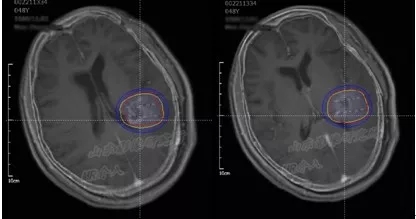

术前TPS计划

山东省医学影像学研究所/磁共振微创介入科的李成利主任在了解满女士的病情后,采取了

磁共振联合个体化平行插植3D打印模板引导I125放射性粒子植入治疗。

3D打印模板术中定位

但是磁共振+3D打印模板+I125粒子植入的创新组合,却是史无前例。

根据满女士的治疗计划,李成利主任找专人制作了颅脑介入手术专用的3D打印引导模板。